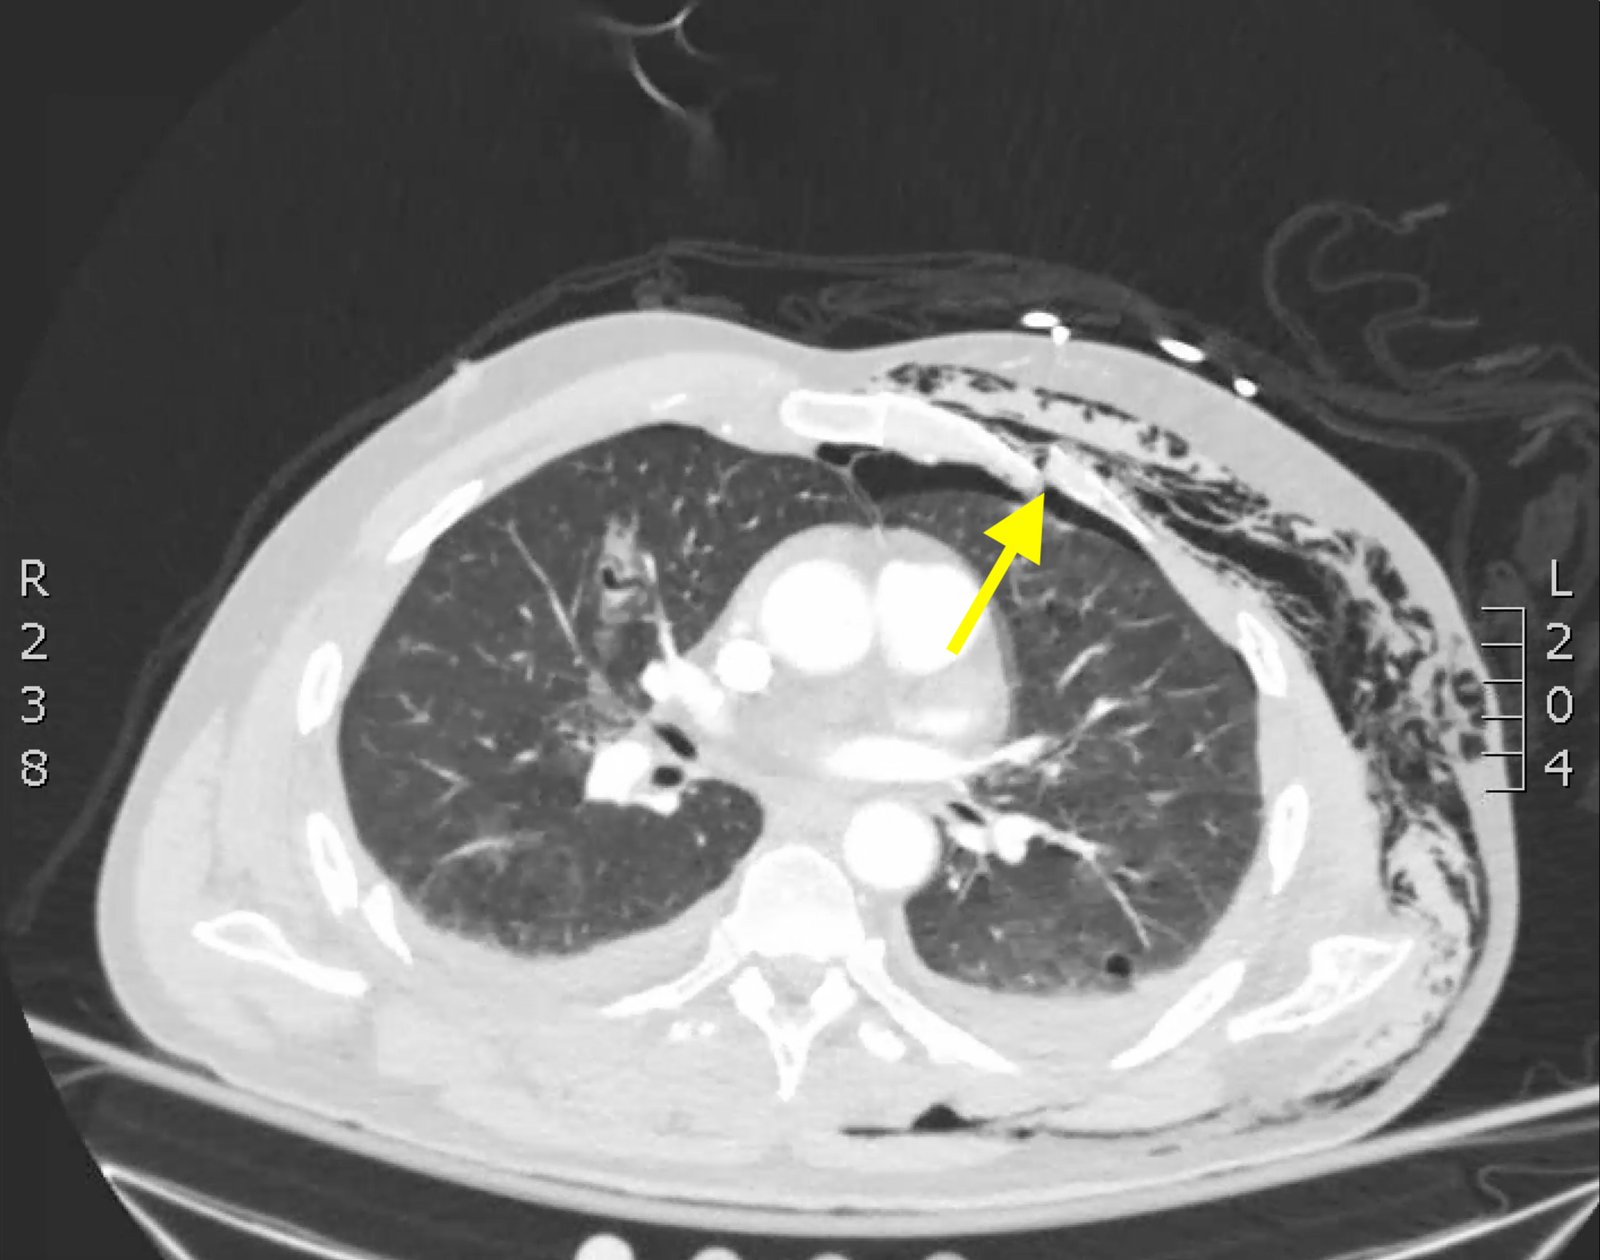

Plain film anteroposterior (AP) radiography of the chest shows left-sided subcutaneous emphysema (red arrow) with overlapping muscle striations of the pectoralis major (green arrow). After chest tube placement (blue arrow), AP chest radiography shows persistent left-sided subcutaneous emphysema (red arrow). CT of the chest shows pneumomediastinum (blue arrow), left apical pneumothorax (pink arrow), and subcutaneous emphysema (red arrow) at the level of T2. At the level of T6, rib fractures can be visualized on the CT (yellow arrow). At the level of T8, left sided pneumothorax is also seen (pink arrow) as the absence of lung tissue on CT.